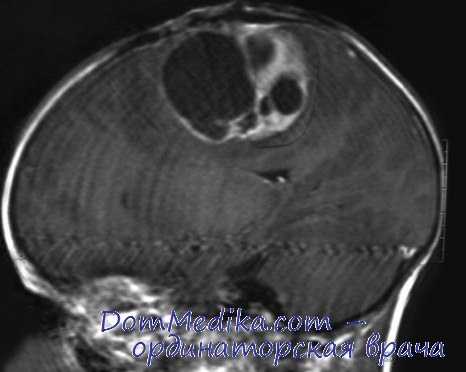

МРТ головного мозга. Аксиальная Т2-взвешенная МРТ. Цветовая обработка изображения. Опухоль мозга.